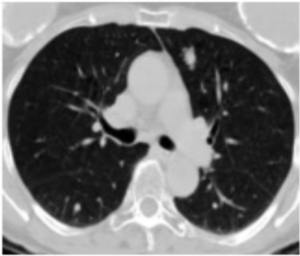

We generate x^*, which only requires slight modification within the area m (see the bottom right of the image). This indicates that f "understands" where in the image the malignant nodule is present. | You: Exactly! And how can you change it to a nine? Paul: I can add a line at the top to make it a nine! You: That's correct, you got it! |